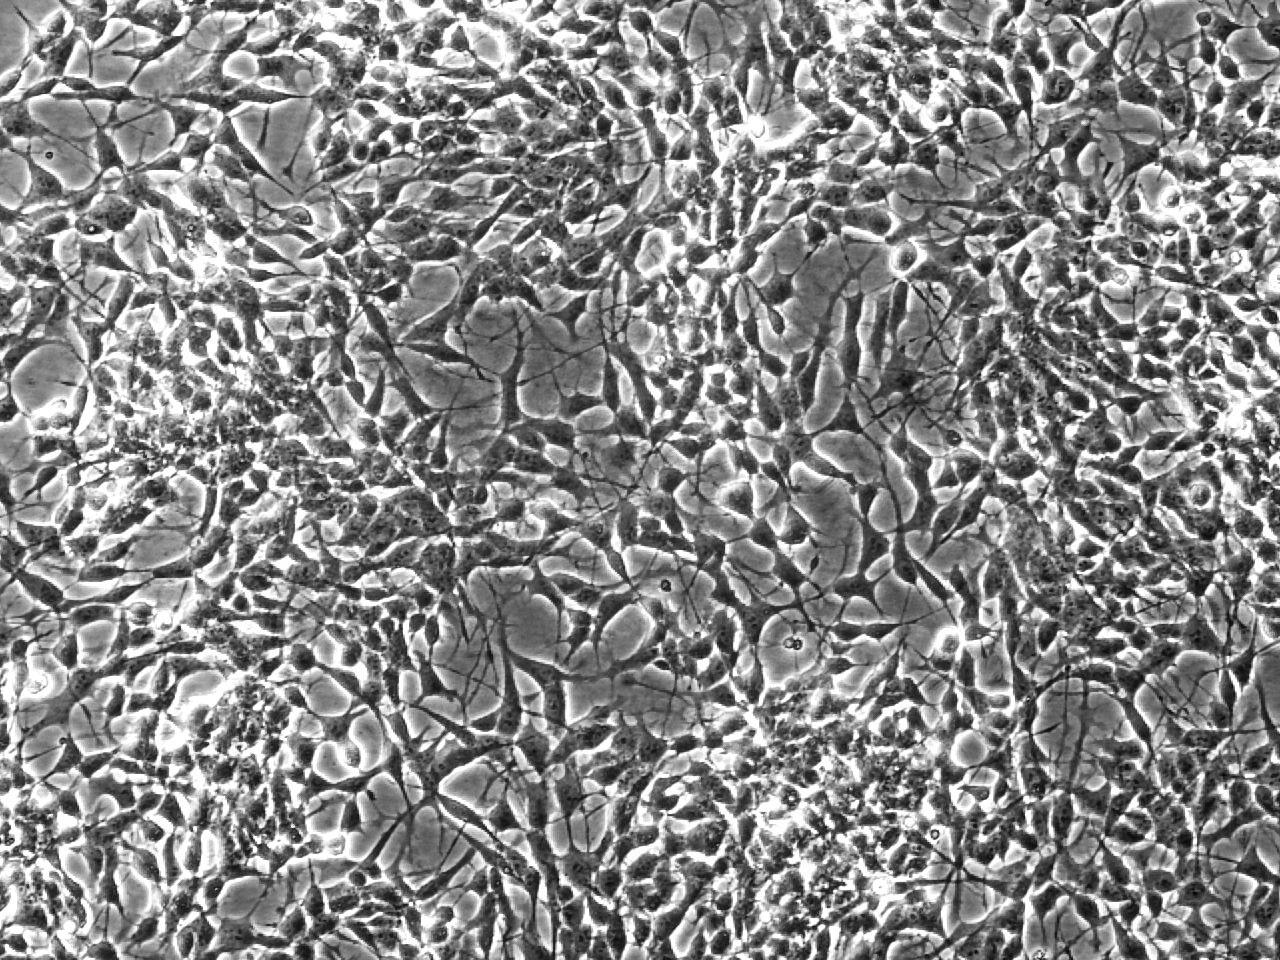

jsc2022e031232 (4/26/2022) --- A preflight view of differentiating neuron-like cell cultures with a dense network of neurites for intercellular interaction. The PROtection MEdiated by antioxidant nanoTEchnOlogy against neuronal damage in space (PROMETEO) (Antioxidant Protection) investigation proposes the use of biocompatible and biodegradable polydopamine-based nanoparticles to provide antioxidant protection to neurons undergoing exposure to altered gravity and cosmic radiation. Image courtesy of Istituto Italiano di Tecnologia.